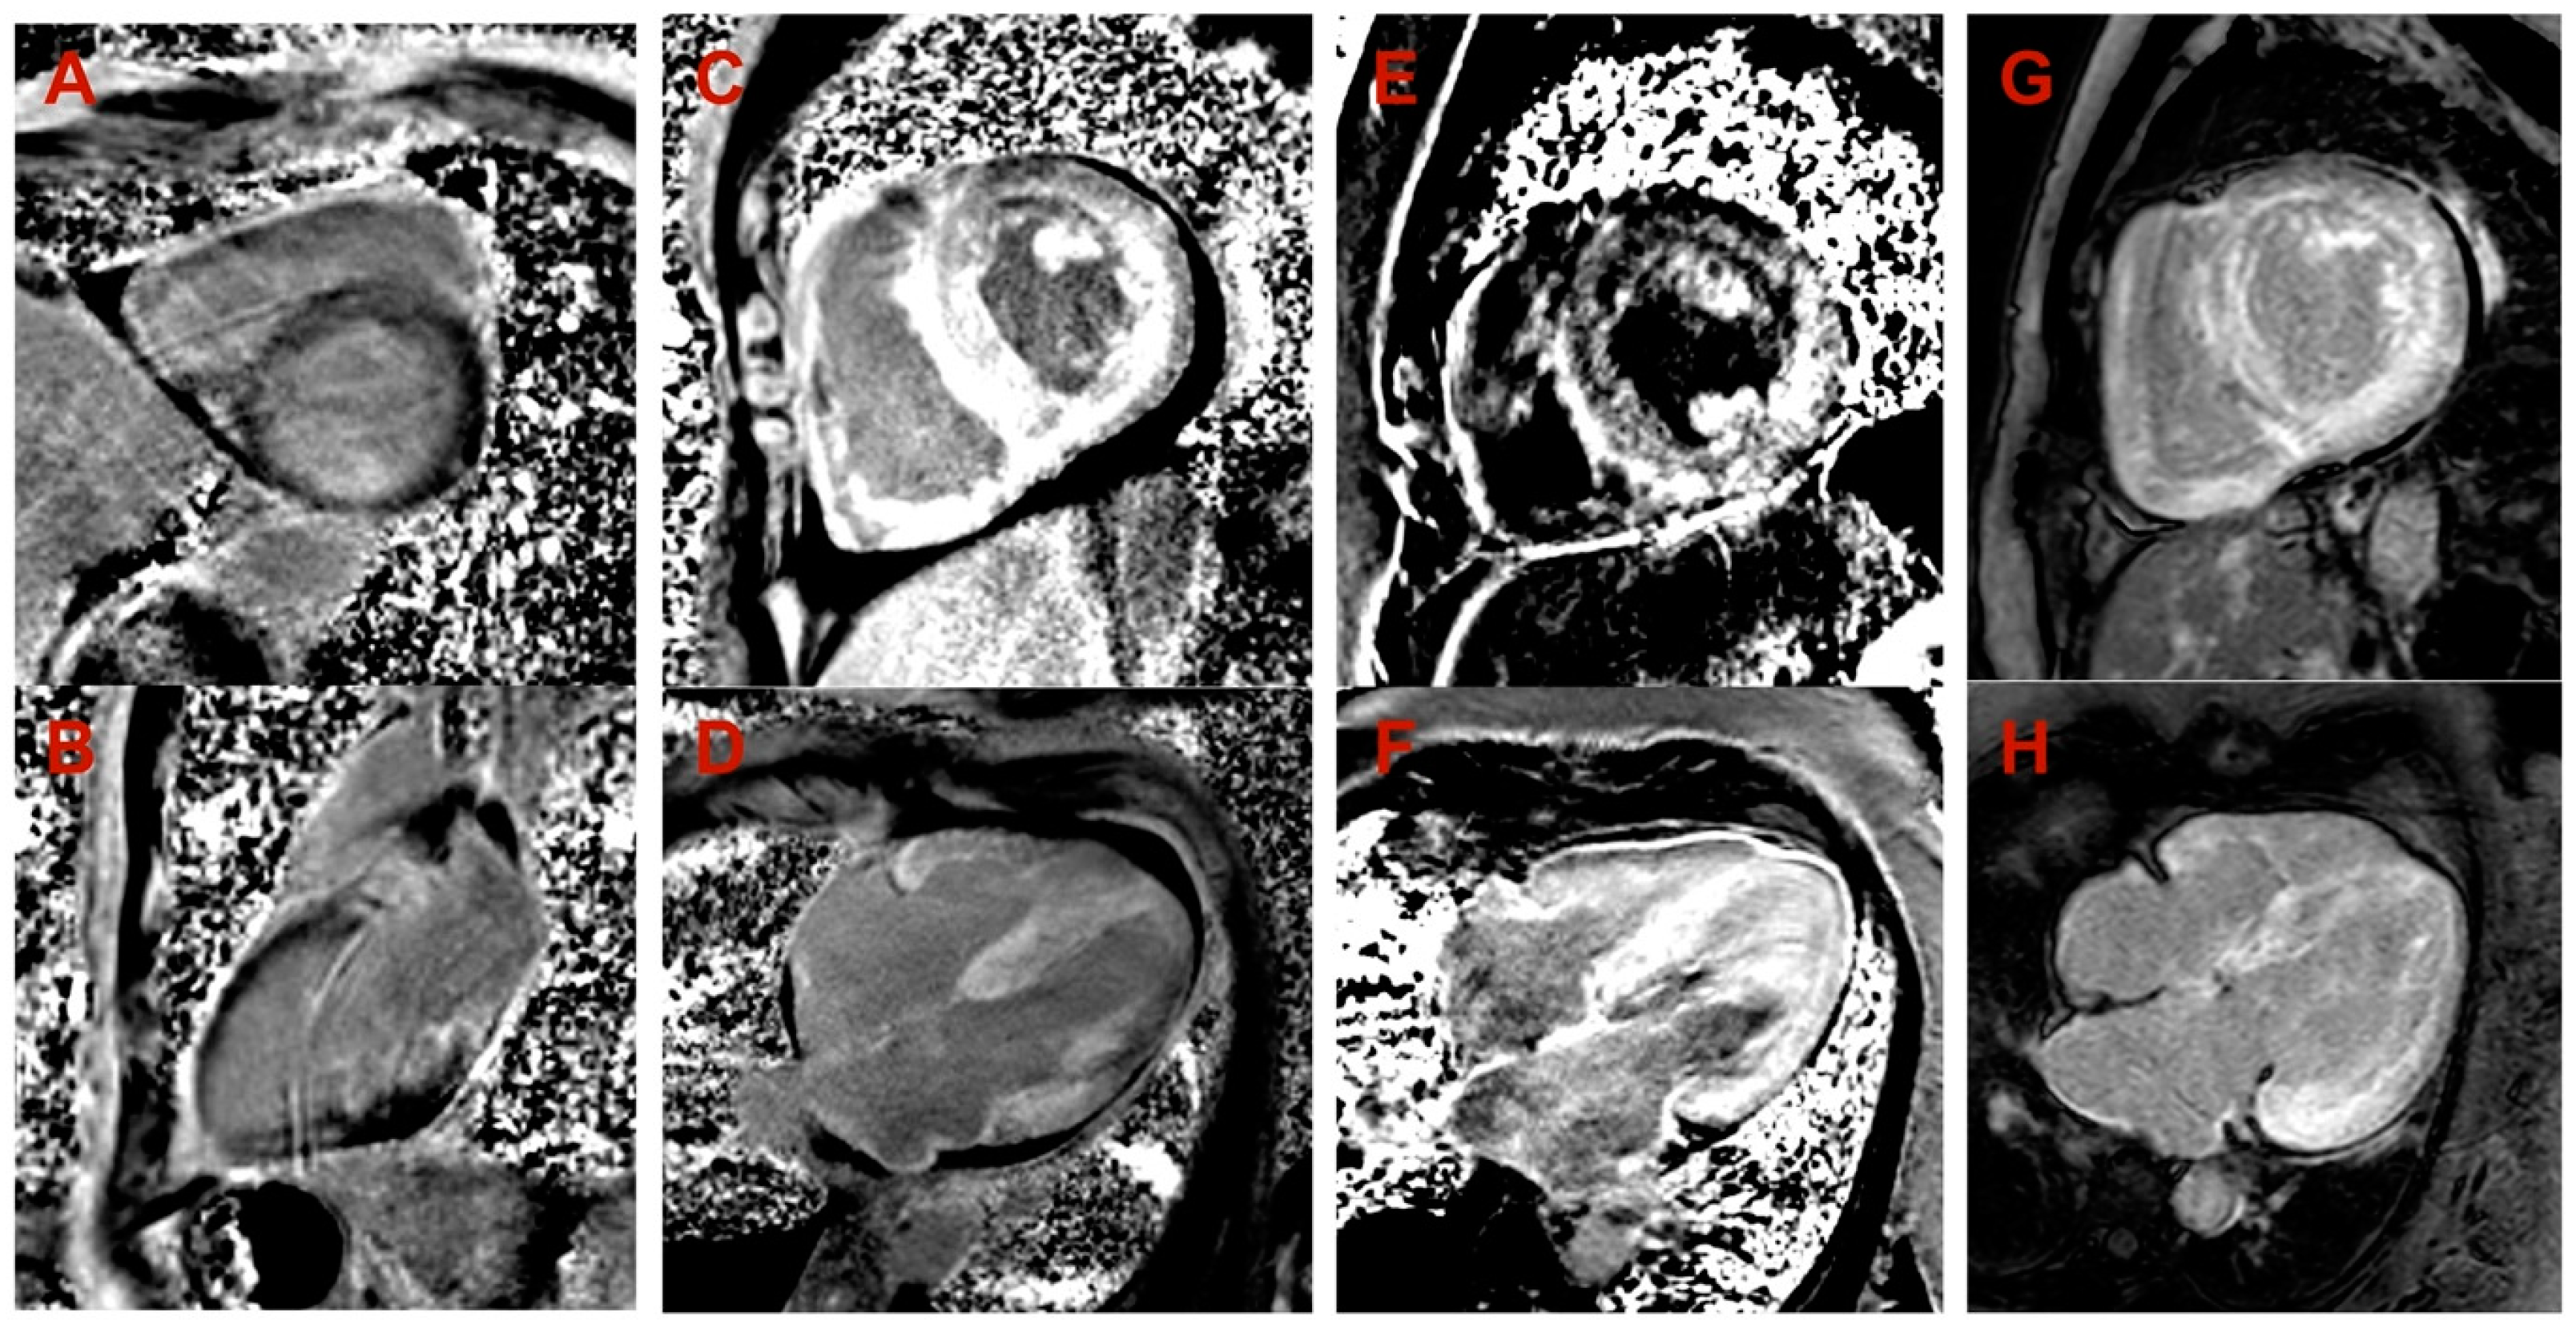

| Cardiac MRI LV hypertrophy | Asymmetric (predominantly in transventricular septum) | Symmetric | Symmetric | Symmetric |

| Cardiac MRI maximal wall thickness (mm) | 16 | 19 | 14 | 20 |

| Cardiac MRI LVEF (%) | 77 | 45 | 50 | 44 |

| Cardiac MRI LGE | Midmyocardial LGE in LV septum and inferior wall | Diffuse subendocardial LGE in LV and RV | Diffuse midmyocardial LGE in LV and RV | Diffuse subendocardial LGE in LV and RV |